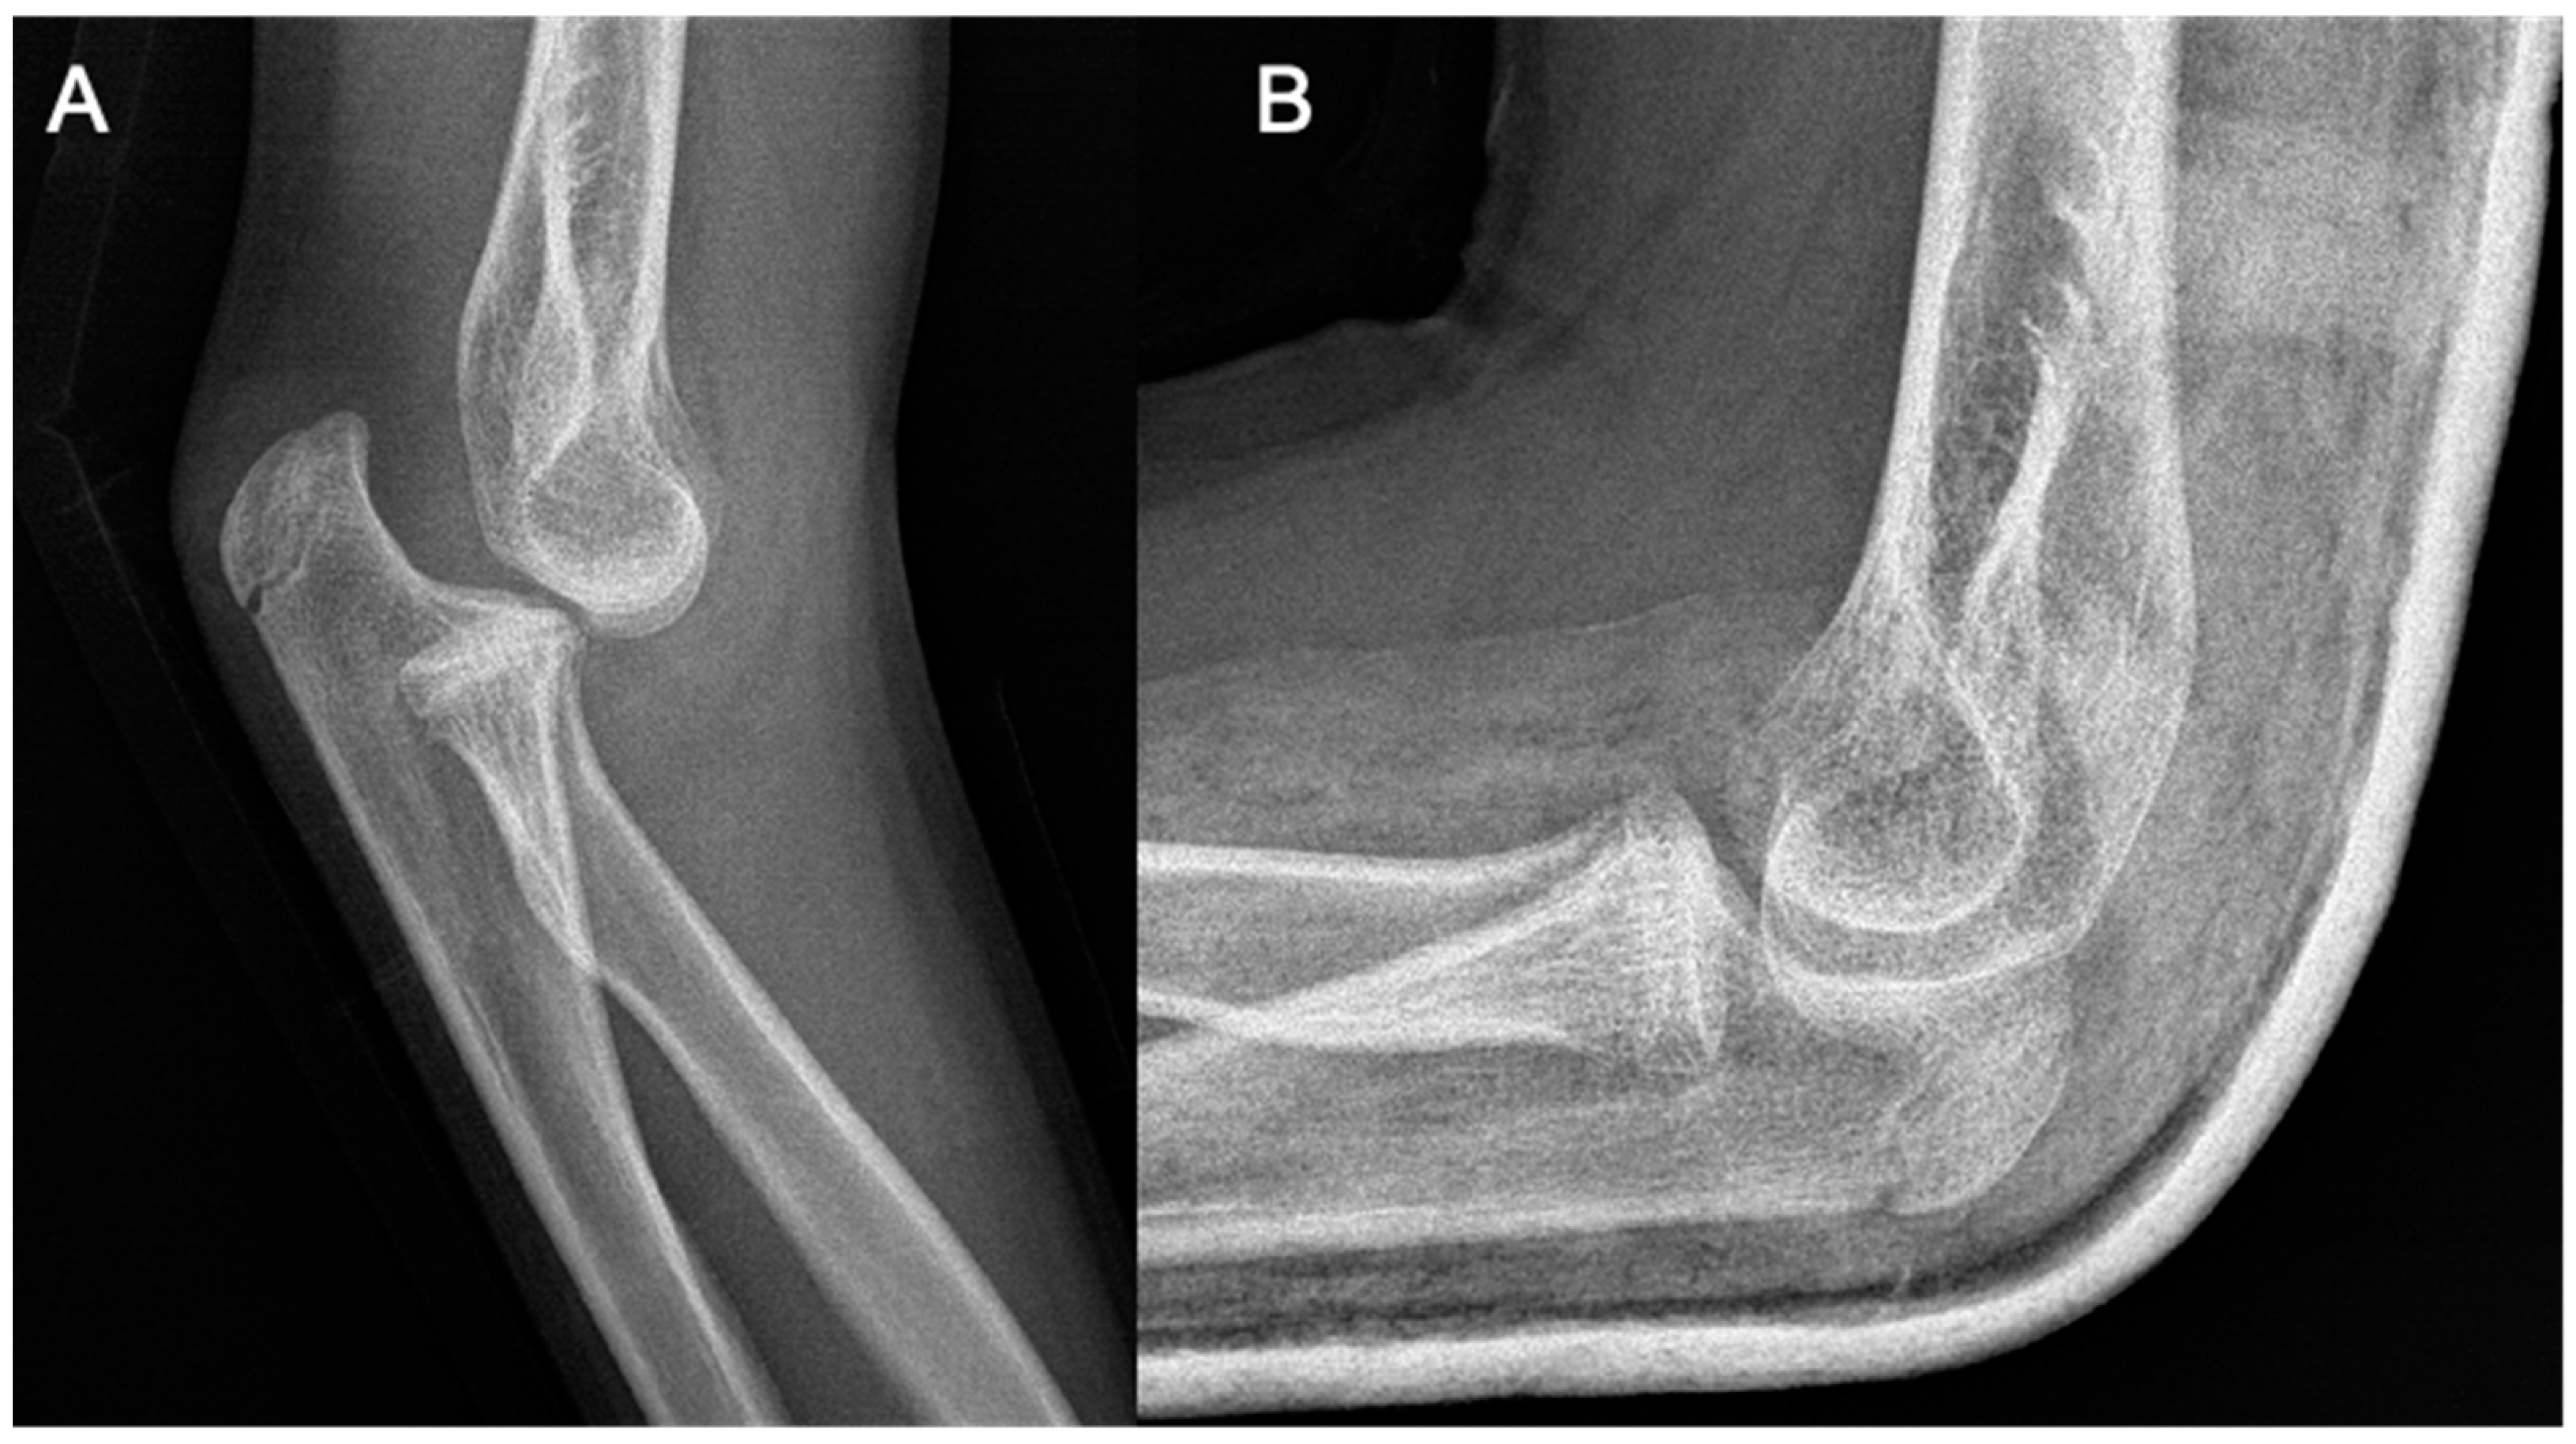

At the age of 13, another injury occurred, and the child complained of a sprain prior to the injury. X-ray imaging showed a posterior elbow dislocation without signs of a fracture (Figure 5). Under anesthesia, the luxation was repositioned. Following repositioning, an image review was performed, and no suspected fracture area was identified. A long upper limb cast was placed for two weeks.

Figure 5. Imaging of the posterior dislocation at age 13, image (A) showing the luxation upon ebow extension and (B) from a lateral view in flexed position.